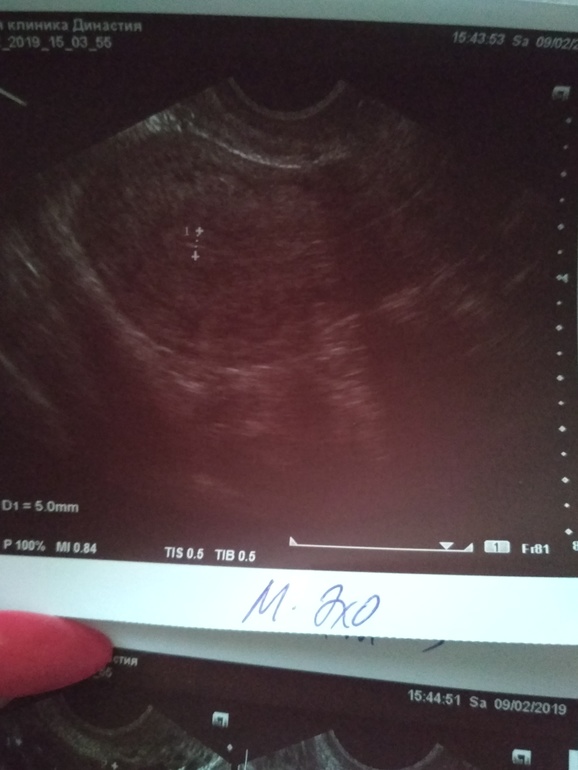

9.02.19 18 ДЦ - 36,6 ( в этот день не выдержала пошла на фолликулометрию...,там мне сказали,что овуляция у меня была...когда непонятно...делала тесты на овуляцию 2 полоска была призрачная...делала тесты с 4.02.19 по 8.02.19 как положено по инструкции. По фолликулометрии вот что сказали: Эндометрий 5 мм однородный,повышенной эхогенности..., в левом яичнике кистозное желтое тело 18*14 мм со слабым кровотоком по периферии (врач узист сказал,что в желтом теле есть немного крови...я ее спросила почему так?? Она толком не ответила,сказала типа нечего страшного так бывает...)., свободная жидкость в позадиматочном пространстве: "следы" жидкости.,ЗАКЛЮЧЕНИЕ: несоответствие эндометрия дню цикла. Овуляторный цикл. Мультифолликулярная эхоструктура яичников.)

Эндометрий.